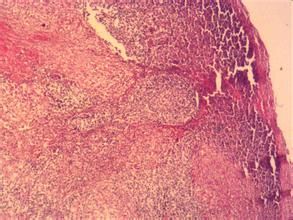

肉芽腫內的巨細胞是由上皮樣細胞融合而來,細胞數目可達幾十個,甚至幾百個。其功能也與上皮樣細胞相似,尚可見於不易消化的較大異物周圍,組織中角化上皮和尿酸鹽等周圍,細胞核雜亂無章的分布於細胞中,又稱異物多核巨細胞。若細胞核排列於細胞的周邊稱為Langhans型巨細胞。此種細胞還可見於由吞噬了結核分枝桿菌的巨噬細胞形成的上皮樣細胞相互融合或一個細胞核分裂胞質不分裂乃形成朗罕斯巨細胞。朗罕斯巨細胞為一種多核巨細胞,直徑可達300微米,胞質豐富。其胞質突起常和上皮樣細胞的胞質突起相連線,核與上皮樣細胞核相似。核的數目由十幾個到幾十個不等,有超過百個者。核排列在胞質周圍呈花環狀、馬蹄形或密集於胞體的一端 。

郎罕巨細胞--為結核結節的組成成分之一,此細胞是由上皮樣細胞聚集而成。

樣細胞區,在上皮樣細胞間存在著少數多巨核細胞(朗格漢斯巨細胞)。有時...淋巴細胞及單核細胞所包繞,中間為上皮樣細胞區,內有少數多核巨細胞(朗格漢斯巨細胞)。其他輔助檢查MRI(磁共振成像)1.乳房X線檢查(1)結節型...